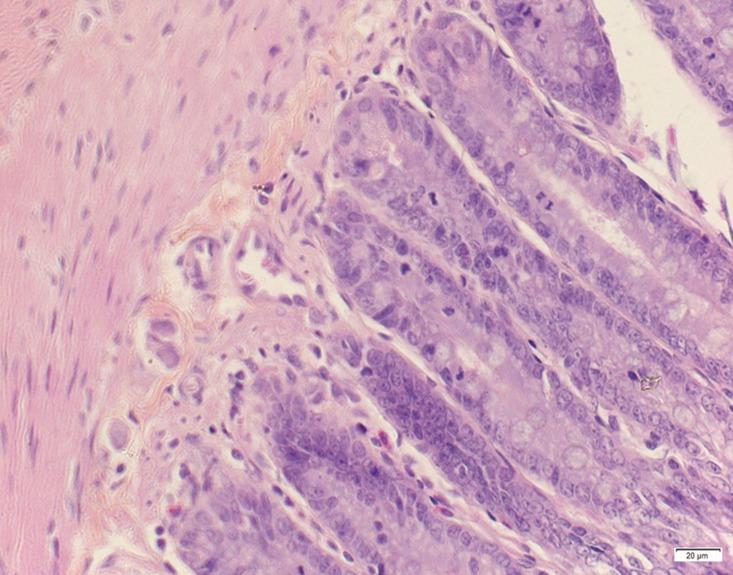

A subchronic toxicity test was conducted in rats on the basis of a previous acute toxicity test to evaluate the safety of arecoline hydrobromide (Ah), to systematically study its pharmacological effects and to provide experimental support for a safe clinical dose. Eighty rats were randomly divided into four groups: a high-dose group (1000 mg/kg), medium-dose group (200 mg/kg), low-dose group (100mg/kg) and blank control group. The doses were administered daily via gastric lavage for 14 consecutive days. There were no significant differences in the low-dose Ah group compared to the control group (P>0.05) with regard to body weight, organ coefficients, hematological parameters and histopathological changes. The high-dose of Ah influenced some of these parameters, which requires further study. The results of this study indicated that a long-term, continuous high dose of Ah was toxic. However, it is safe to use Ah according to the clinically recommended dosing parameters. The level of Ah at which no adverse effects were observed was 100 mg/kg/day under the present study conditions.